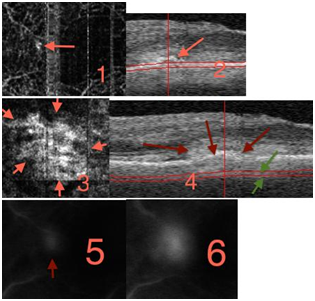

The process of Angio-OCT is very simple, it needs nearly the same cooperation and acquisition time than a common OCT, we can consider that this method could be extend nearly at every on Angio-OCT is motion and eye blink sensitive, but the correction of these parameters are really efficient with the news software’s, we can carry out Angio OCT in 9 cases on 10. First is a normal subject, 75 old (Figure 1), to be schematic in this presentation you can observe 4 different layers, two retinals: superficial and deep which is more medial (inner plexiform layer) and two choroidal: external retina with retinal pigment epithelium (RPE) and choriocapillaris (CC). The accuracy of the picture is real, you have a very good visualization of the peri foveolar capillaries, you discover the deep retinal vessels, densest and twisted, and then you reach the external retina avascular layer, to finish with the CC dapple-grey aspect. You can compare with OCT images to complete your diagnosis, and the level of the layer is showed on the OCT (between red and green line reported on the OCT). The first very enthusiastic Angio OCT are provided by wet complications of macular degeneration.

Figure 1 Normal patient 75.

No abnormal «flow» signal is present, normal vessels are well individualized; choriocapillaris lobules are shown like clusters of half light signal. For now the best images we can obtain are 3X3 mm, possibly 6X6 mm and as a result of which the main use is centered on macula, and on ARMD In this case of subretinal new vessel which is a minimally classic choroidal new vessel7 (Figure 2) you can clearly see an abnormal flow signal pointed in red, followed by the OCT, confirmed by AF In one shot you diagnose a choroidal neovascularization and you replace AF and indocyanine green angiography (ICG). Angio OCT is also very contributive for retinal angiomatous proliferation (RAP), you can analyze your different layer and determine the course of the rap and nearly the complete morphology of the lesion. The analysis of the RAP could begin from the internal retina to the choroid In rap you observe at the retinal level, a deviation and dilation of retinal vessels in outer and medial retina (Figure 3) then you reach the anastomosis (Figure 4(1)) and the shape of the angiomatous lesion and nearly the total morphology of it (Figure 4(2,3)), the images are really better and more didactic than ICG and FA (Figure 5(1−3). The follow up of new vessels is also very interesting, with the confrontation of OCT you can easily highlight the activity of the new vessels (anastomosis, reflectance) and the regression of this activity after treatment (Figure 5−8) with sometimes very impressive images of «resting» new vessels (Figure 8,9) Angio OCT is also helpful to affirm the non vascular activity of a pigment epithelium detachment (Figure 10).

Figure 2 Minimally classic cmv: 1and 2 retinal layer, 3 et 4 CC level (green arrow) 5 FA 24s 6 FA 1’19.